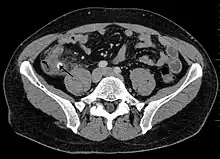

Computed tomography

Where it is readily available, computed tomography (CT) has become frequently used, especially in people whose diagnosis is not obvious on history and physical examination. Concerns about radiation tend to limit use of CT in pregnant women and children, especially with the increasingly widespread usage of MRI.[49][50]

The accurate diagnosis of appendicitis is multi-tiered, with the size of the appendix having the strongest positive predictive value, while indirect features can either increase or decrease sensitivity and specificity. A size of over 6 mm is both 95% sensitive and specific for appendicitis.[51]

However, because the appendix can be filled with fecal material, causing intraluminal distention, this criterion has shown limited utility in more recent meta-analyses.[52] This is as opposed to ultrasound, in which the wall of the appendix can be more easily distinguished from intraluminal feces. In such scenarios, ancillary features such as increased wall enhancement as compared to adjacent bowel and inflammation of the surrounding fat, or fat stranding, can be supportive of the diagnosis. However, their absence does not preclude it. In severe cases with perforation, an adjacent phlegmon or abscess can be seen. Dense fluid layering in the pelvis can also result, related to either pus or enteric spillage. When patients are thin or younger, the relative absence of fat can make the appendix and surrounding fat stranding difficult to see.[52]